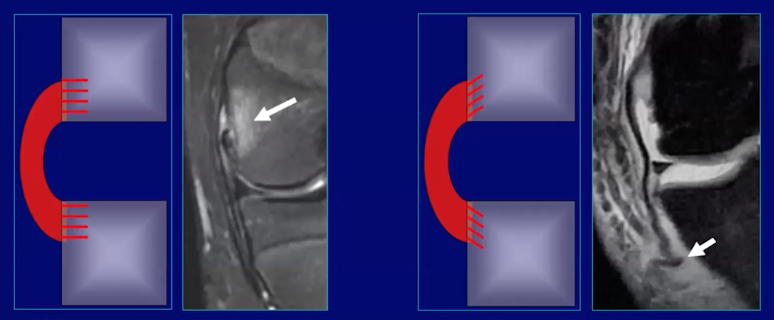

Ligaments

• Direct insertion (left)

• Ligament attaches to cortex of bone at right angles

• Will result in marrow edema with injury

• i.e. MCL femoral attachment, ACL tibial attachment

• Indirect insertion (right)

• Ligament attaches to cortex at oblique angles

• Tend not to have marrow edema with injury

• i.e. tibial insertion of MCL